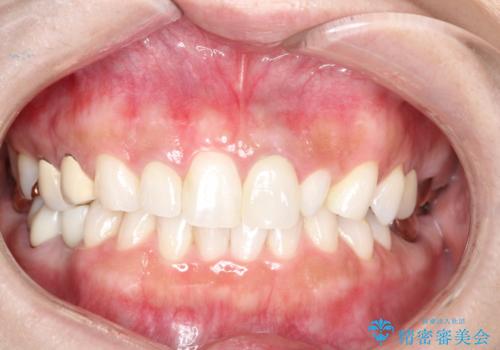

[根管治療・セラミッククラウン] 前歯の痛み・見た目を改善したい

![[根管治療・セラミッククラウン] 前歯の痛み・見た目を改善したいの症例 治療前](https://seimitsushinbi.jp/wp/wp-content/uploads/2021/10/27aece2ee2a0fb95849ae035eabf5926-500x350.jpg?v=1633830098)

![[根管治療・セラミッククラウン] 前歯の痛み・見た目を改善したいの症例 治療後](https://seimitsushinbi.jp/wp/wp-content/uploads/2021/10/969aa8878a18bb42608c420b34b6b67f-500x350.jpg?v=1633830182)